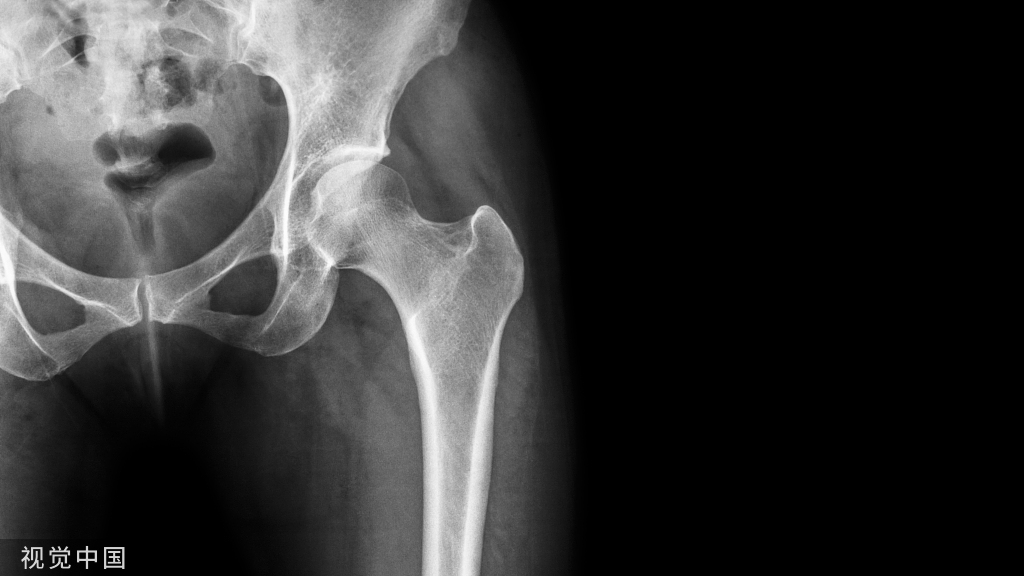

1.骨折时损伤有一定的报道提示骨盆骨折时该血管断裂损伤,尤其是在耻骨支外4-6cm处骨折时需要注意。

1.受伤时怀疑损伤可以做CT,腹部B超,腹腔穿刺等来进行诊断,B超的敏感性不强,CT有时可以发现耻骨附近的血肿。实在不行可以做造影。

一个老年女性患者骨盆骨折,没有移位,住院后给予保守治疗后出院,出院三天后在上厕所时,腹部疼痛、尿少、心动过速、血压减低,立即入院后查体发现下腹部疼痛,压痛反跳痛,腹膜炎表现。

行CT,发现腹腔有10*10*15的血肿位于耻骨骨折旁边。